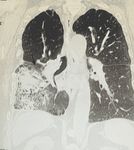

Chest radiograph (CXR) done on the same day showed interval development of consolidation involving the

2022 Haridi et al. Cureus 14(5): e24760. DOI 10.7759/cureus.24760 2 of 5FIGURE 1: Chest x-ray demonstrating right lung opacity

Arrow indicates the infiltrate